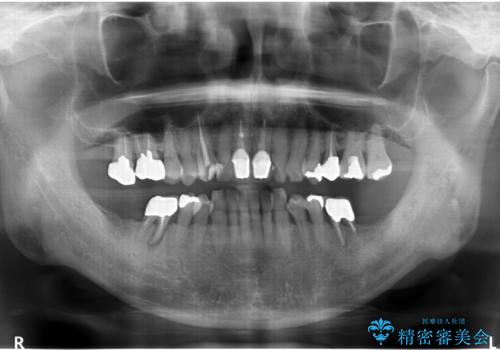

- 右下の奥歯が割れてしまい、抜歯を行いました。

ブリッジにできない位置であったため、インプラントでかめるようにしました。

また、向かい合う上の歯が挺出(伸び出してしまうこと)しており、インプラントを入れることが難しかったため、長さを短くかぶせ治しました。

また、上顎前歯以外の根の治療のやり直しを行いました。

上顎前歯は他院で根管治療とセラミックを行なったとのことで、歯肉縁下形成のため、歯肉の腫れが治りにくい状況でしたがやり直しは希望されませんでした。

左下に関しては、経過観察を行い、歯が割れたりした場合にインプラントを考えることになりました。

- 約250万円 右下67 インプラント2本(ストローマンインプラント20万円、カスタムアバットメント10万円、シリンダーTeC 2万円 以上2本、マイナーGBR5万円) 再根管治療 (前歯 9万円x1、小臼歯11万円x1 大臼歯:専門医による再治療 15万円x3本) ジルコニアクラウン(右上2367、右下I6I7、左上56 10万円x8 )仮歯 1万円x8本 ファイバーコア 2万円x5 セラミックインレー(左上5) 7万円x1 フラットタイプナイトガード 3万円費用は治療当時の料金となります